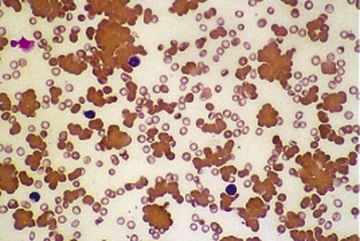

Chronic myelogenous leukemia has a very characteristic blood smear (Fig. 157-26) in which the most numerous cells are myelocytes and mature neutrophils. Eosinophils and basophils are also present. Dysplastic features are generally absent. In atypical Philadelphia chromosome–negative chronic myeloid leukemia, monocytosis is more frequent and dysplastic features are present. Chronic myelomonocytic leukemia is characterized by increased monocytes, some of them immature, with inconspicuous dysplastic features and infrequent granulocyte precursors.